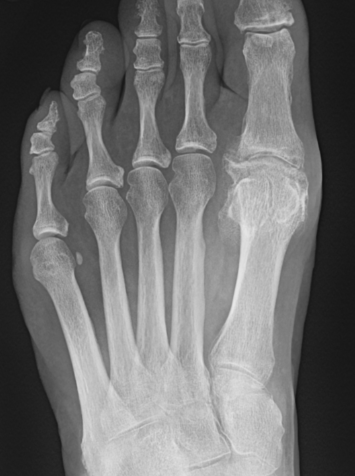

X-ray

Osteoarthritis

- joint space narrowing

- dorsomedial osteophyte

Mild to moderate OA